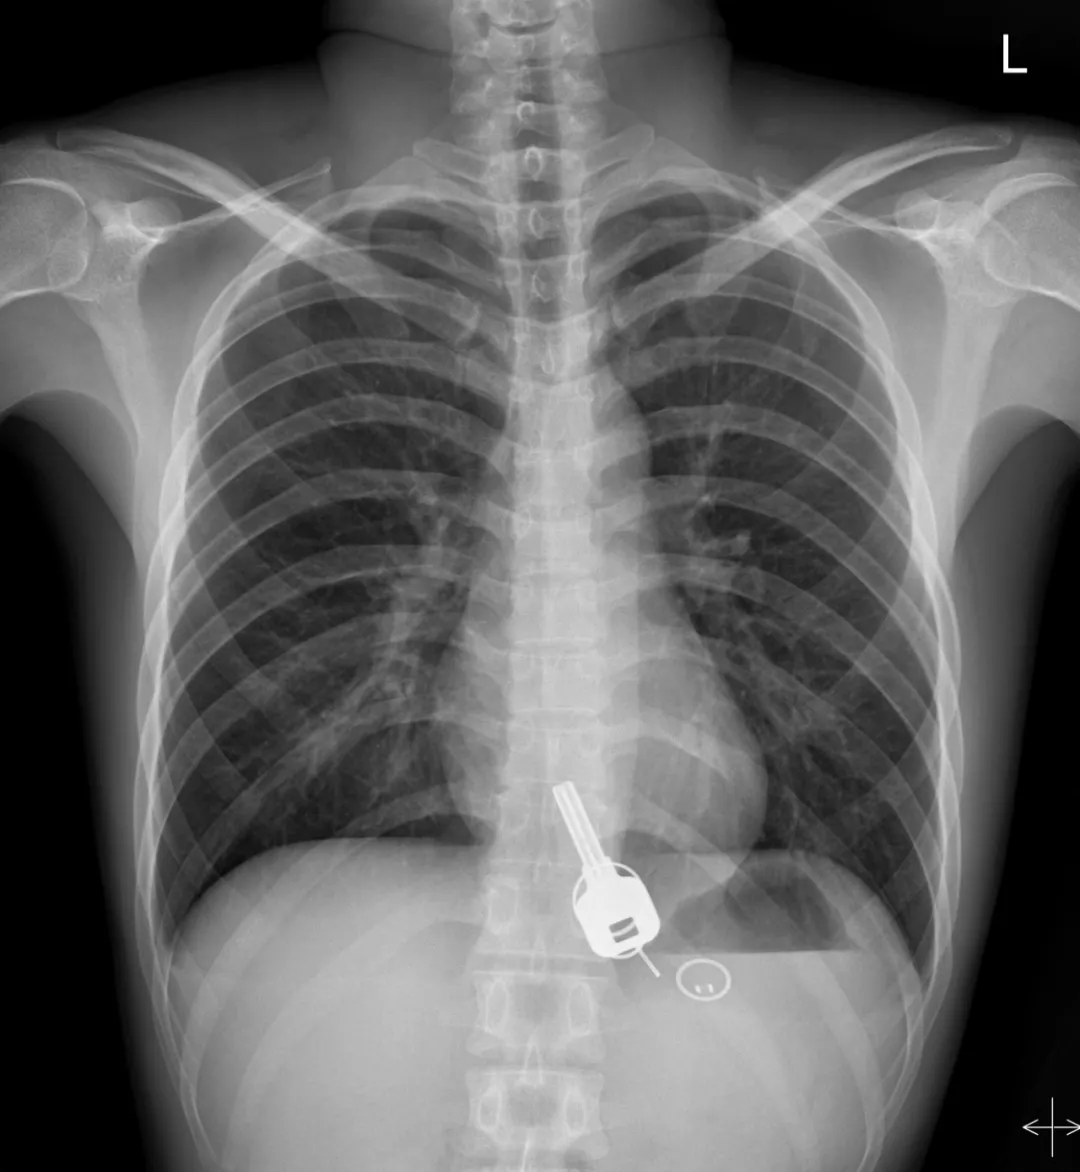

廣東東莞的常先生酒后回家找不到鑰匙,酒醒后他感到胸口疼痛,去醫(yī)院一查,發(fā)現(xiàn)一把鐵鑰匙、2個鑰匙扣、1個門禁牌清楚顯示在肚子胃區(qū)的位置上。

醫(yī)生準備在胃鏡下取出鑰匙,不料,因鑰匙太大在常先生喉嚨附近食管入口處卡住了,取不出來,最后,醫(yī)生決定給常先生做無痛胃鏡,麻醉后,常先生食管入口處肌肉松弛,鑰匙終于順利取出!。